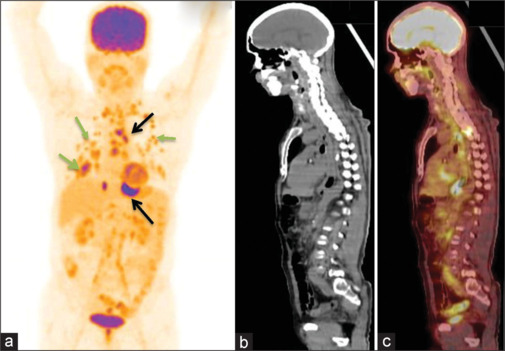

Results: Among total n = 74 (42 males and 32 females with mean age 59.4 ± 11.4; range 35-86 years) patients, SCC was seen in 78.4% and AC in 21.6% of patients. There is a progressively increased SUVmax value of primary tumor with nodal and distant metastases. 18F-FDG PET/CT showed disease of Stage I-II in 12.1%, Stage III in 20.2%, Stage IVA in 25.6%, and Stage IVB in 41.8% patients. There is agreement between 18F-FDG PET/CT and CECT chest and abdomen in the evaluation of regional lymph nodes (37.8% vs. 36.4%; κ - 0.96), nonregional lymph nodes (24.3% vs. 20.2%; κ -0.74), and distant organ involvement (21.6% vs. 17.5%; κ -0.82). In addition, 18F-FDG PET/CT found synchronous malignancies in 4.0% of patients.

Conclusion: 18F-FDG PET/CT metabolic parameters help in identifying metastatic involvement in morphologically equivocal and clinically suspicious lesions in carcinoma esophagus patients. Being a whole-body imaging modality, 18F-FDG PET/CT has inbuilt advantage to detect occult, distant metastases, and synchronous malignancies for effective staging and improving plan of clinical management.